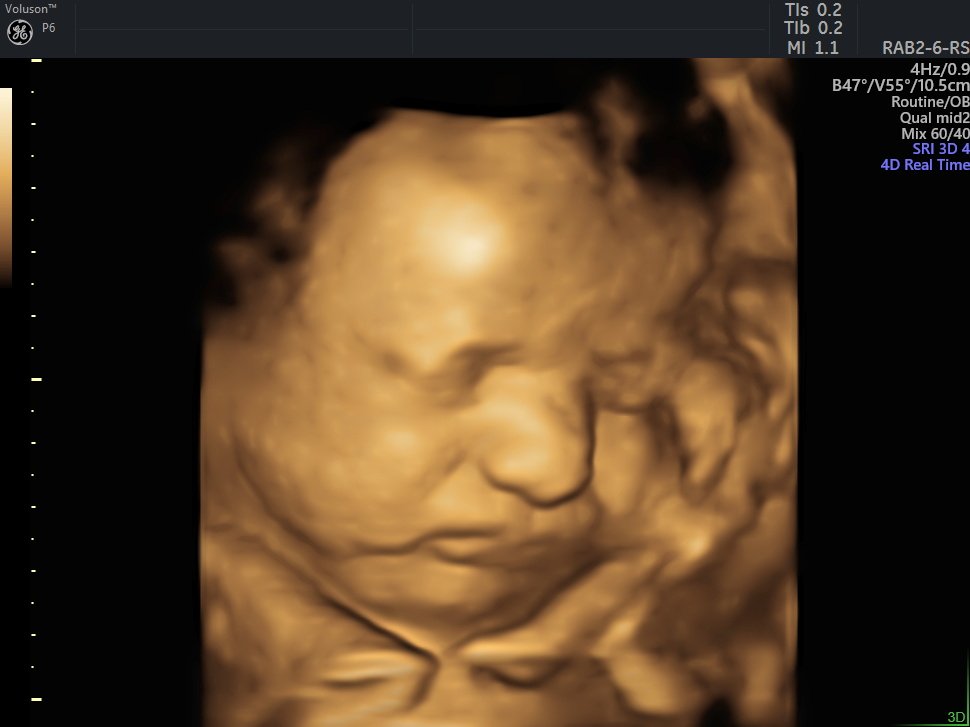

4 D Ultrasonografi

4 Boyutlu (Renkli) Ultrason ve Doppler Ultrasonografi